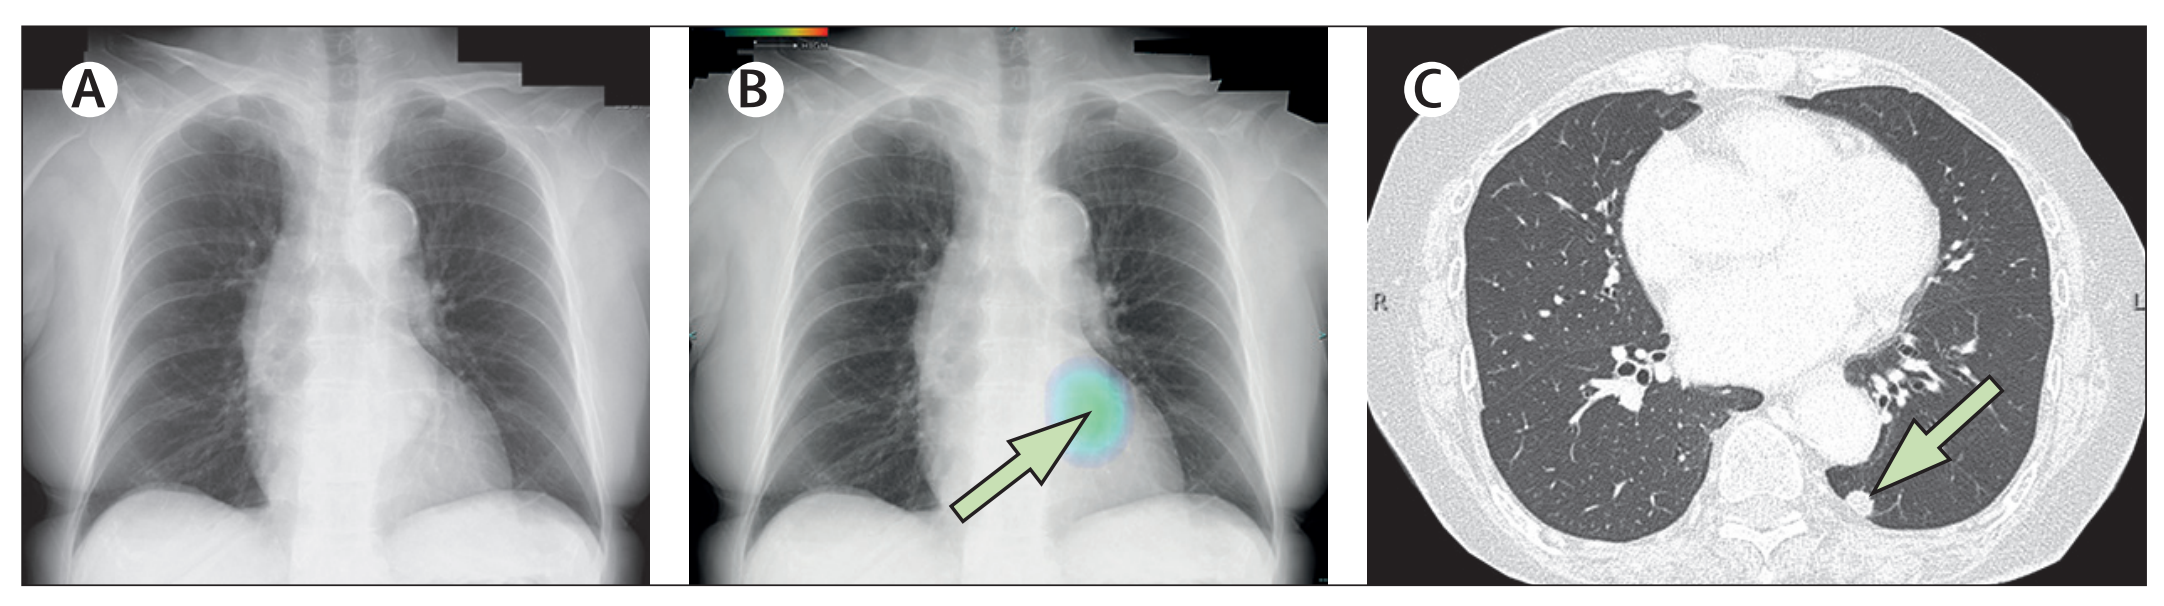

Fig. 1 展示了非小细胞肺癌(NSCLC)异质性的单细胞转录组学分析结果。

以下是对图中各个部分的分析:

A. 研究概述:从切除的肿瘤组织、邻近未受累组织(背景)以及已故捐赠者的健康肺中制备了单细胞悬浮液,并富集了CD45+或CD235-的细胞进行单细胞RNA测序(scRNA-seq)。使用新鲜冷冻的肿瘤、背景和健康组织的冷冻切片进行10x Genomics Visium空间转录组学研究。

B. 队列概览:符号代表了个体患者以及执行的分析。

C. UMAP投影:展示了肿瘤和结合背景+健康数据集的UMAP(Uniform Manifold Approximation and Projection)投影图,这是一种用于降维和数据可视化的技术。

D. 点图(Dotplot):显示了用于肿瘤样本中宽泛细胞类型注释的代表性基因。点图通常用于展示基因表达水平,点的大小代表表达量,颜色代表表达水平的变化。

E. 等高线图(Contour plot):展示了在AT2细胞(44,399个细胞)、CAMLs(2520个细胞)和AIMφ(16,120个细胞)中共表达的髓系(LYZ, CD68, MRC1)和上皮系(EPCAM)基因。这些数据被标准化、缩放和对数转换。

F. 箱线图(Boxplot):展示了在AT2细胞、CAMLs和AIMφ中髓系(LYZ, APOE, CD68, MRC1)和上皮系(EPCAM, KRT8, KRT19)基因的标准化、缩放和对数转换后的基因表达。箱形图显示了四分位数,须表示1.5倍四分位距。

G. 非免疫细胞亚群的相对比例:在CD235-富集中计算的肿瘤与背景之间的差异。箭头指示了肿瘤与背景相比的增加(↑)或减少(↓)。使用双边Wilcoxon秩和检验和Bonferroni校正进行多重比较。**P < 0.01。没有星号的箭头表示该细胞类型仅在肿瘤或背景中发现。

H. 广泛免疫细胞的相对比例:在所有免疫细胞中识别的CD235-富集中计算的肿瘤与背景之间的差异。箭头指示了肿瘤与背景相比的增加(↑)或减少(↓)。使用双边Wilcoxon秩和检验和Bonferroni校正进行多重比较。*P < 0.05, **P < 0.01, ***P < 0.001。没有星号的箭头表示该细胞类型仅在肿瘤或背景中发现。

I. 肿瘤和背景中NK、DC、B、T细胞和巨噬细胞亚群的相对比例:在CD235-富集中计算的广泛注释内的肿瘤与背景之间的差异。箭头指示了肿瘤与背景相比的增加(↑)或减少(↓)。使用双边Wilcoxon秩和检验和Bonferroni校正进行多重比较。***P < 0.001。没有星号的箭头表示该细胞类型仅在肿瘤或背景中发现。

总体而言,Fig. 1 通过单细胞转录组学和空间转录组学技术,揭示了肿瘤组织与邻近正常组织在不同细胞类型上的异质性和差异。这些结果有助于深入理解肿瘤微环境中细胞的复杂性,并为未来的治疗策略提供潜在的靶点。